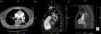

A central bilateral intraluminal filling defect (arrows) is seen, consistent with pulmonary emboli (A – transaxial view; B and C – sagittal views). A thromboembolus (arrowhead) is also seen in the right atrium (C). IVC: inferior vena cava; LV: left ventricle; RA: right atrium; RV: right ventricle; SVC: superior vena cava.